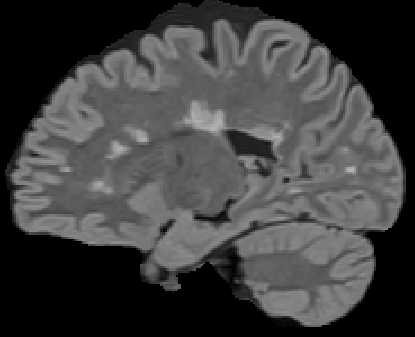

Recently, segmentation methods based on Convolutional Neural Networks (CNNs) showed promising performance in automatic Multiple Sclerosis (MS) lesions segmentation. These techniques have even outperformed human experts in controlled evaluation conditions such as Longitudinal MS Lesion Segmentation Challenge (ISBI Challenge). However state-of-the-art approaches trained to perform well on highly-controlled datasets fail to generalize on clinical data from unseen datasets. Instead of proposing another improvement of the segmentation accuracy, we propose a novel method robust to domain shift and performing well on unseen datasets, called DeepLesionBrain (DLB). This generalization property results from three main contributions. First, DLB is based on a large group of compact 3D CNNs. This spatially distributed strategy ensures a robust prediction despite the risk of generalization failure of some individual networks. Second, DLB includes a new image quality data augmentation to reduce dependency to training data specificity (e.g., acquisition protocol). Finally, to learn a more generalizable representation of MS lesions, we propose a hierarchical specialization learning (HSL). HSL is performed by pre-training a generic network over the whole brain, before using its weights as initialization to locally specialized networks. By this end, DLB learns both generic features extracted at global image level and specific features extracted at local image level. DLB generalization was validated in cross-dataset experiments on MSSEG'16, ISBI challenge, and in-house datasets. During experiments, DLB showed higher segmentation accuracy, better segmentation consistency and greater generalization performance compared to state-of-the-art methods. Therefore, DLB offers a robust framework well-suited for clinical practice.